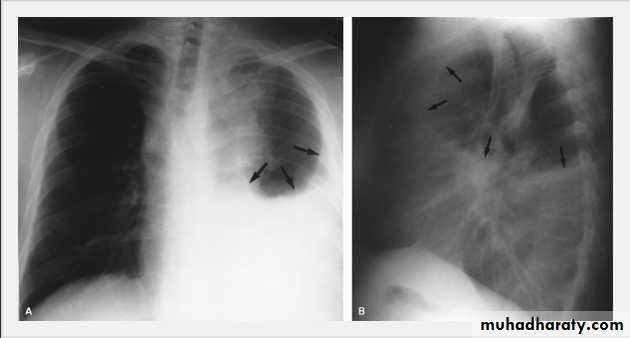

Pleural Effusion on Chest Radiographs.

Posteroanterior (A) and lateral (B) chest radiographs demonstrate the typical meniscoid appearance (arrows) in a patient with a left pleural effusion